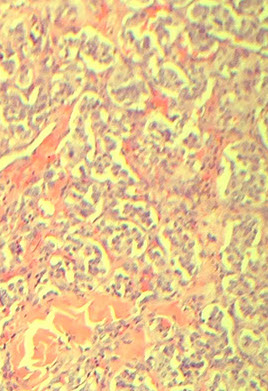

Choroid Plexus Papilloma

WHO grade I

Tumor closely resembles normal choroid plexus, except it forms a mass

- can see hydrocephalus due to CSF overproduction or obstruction, although generally behaves in a benign manner

85% seen in kids (~10 yo), intraventricular (lateral ventricles) tumor

Micro: Benign papillary tumor

- distinguish from normal choroid plexus by closely inspecting the lining epithelium

-- normal choroid plexus is lined by taller columnar epithlium which is smooth, but lacks the undulating surface of normal choroid plexus epithelium which is smooth and lacks the undulating surface of normal choroid plexus

- there should be no signoficant atypia and mits should be absent or rare

IHC: (+) CAM5.2 (94%), transthyretin (89%), GFAP, Kir71

- usually negative p53 and CK20

- CAM5.2 good bc ventricle only epithelial structure in brain, which can stain c CAM5.2